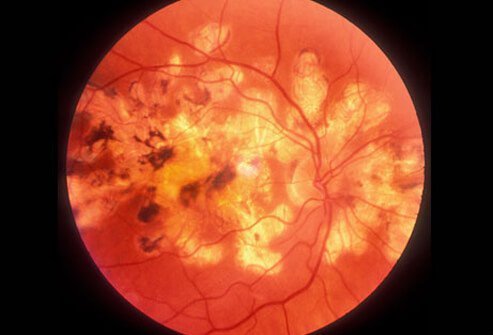

Glaucoma on the Rise

Look Out for Your Eyes

Glaucoma is a condition that involves the build up of pressure inside the eyes. It is dangerous because it may lead to damage to the optic nerve or even blindness. Glaucoma can sneak up on people and may not produce any symptoms until vision has already been damaged. Women should be checked for glaucoma every 2 to 4 years prior to age 40. Between the ages of 40 and 54, exams should occur every 1 to 3 years. Women aged 55 to 64 should be checked every 1 to 2 years. Those who are older than 65 should be checked for glaucoma every 6 to 12 months.

Glaucoma Evaluation

Who Develops Glaucoma?

Certain people are more predisposed to developing glaucoma than others. Those who are Hispanic or African-American or over the age of 60 are more likely to develop glaucoma. The presence of an eye injury, steroid use, or a family history of glaucoma also suggest a higher likelihood of the condition. All women should have a baseline eye exam to assess eye health and the possibility of glaucoma by age 40. All women should get eye exams according to the schedule outlined by their ophthalmologist.